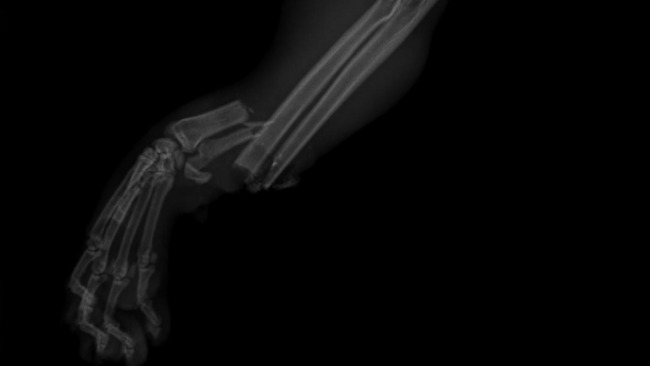

bardzo miły i przyjazny kotek Łatek prosi o wsparcie w leczeniu ma ciężkie złamanie łapki( prawdopodobnie potrącenie przez samochód), które jest bardzo kosztowne, ponieważ musi być leczenie chirurgiczne plus rehabilitacja. Łatek za każdy grosik będzie bardzo wdzięczny gdyż przywróci go do pełnej radości z życia, które niedawno stracił...